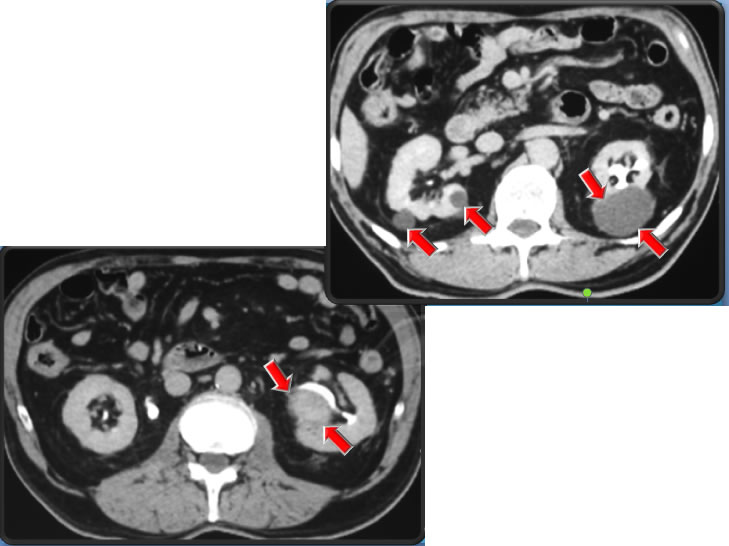

Папилломы и кисты почек - фото презентация